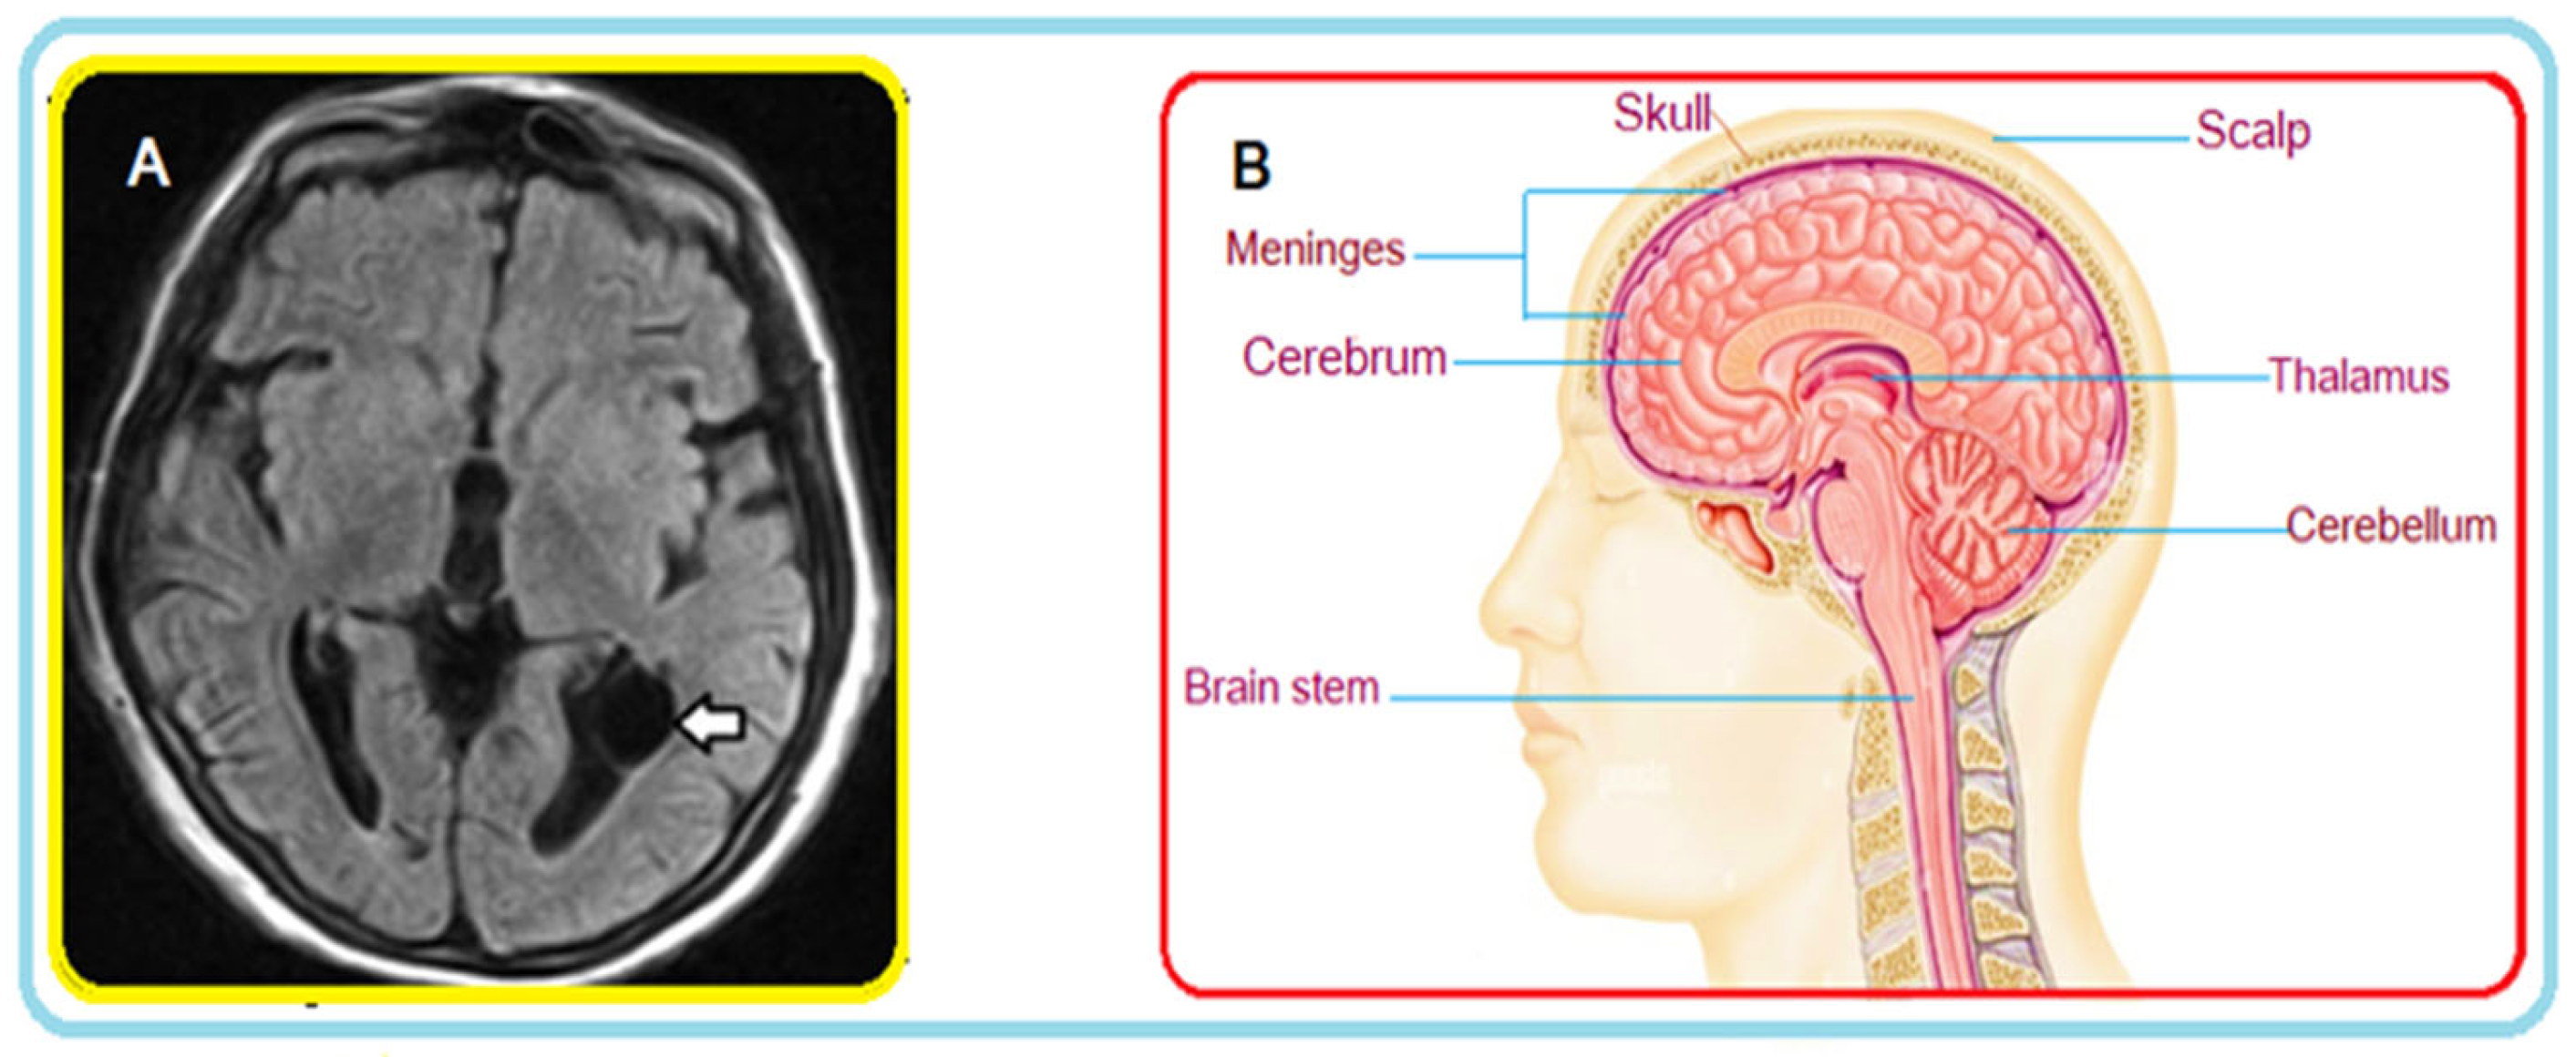

1.1. What Is a Brain Tumor?

1.2. MRI Sequences for Brain Tumors